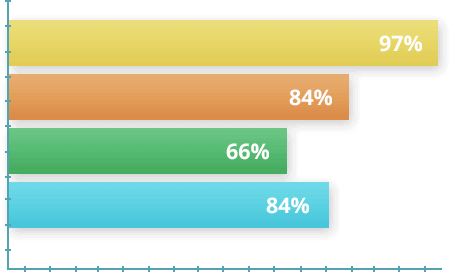

MUSTAQIL TADQIQOTLAR

2017 yilda qo'shma kasallikning turli darajadagi e'tiborsizligi bo'lgan 1700 ko'ngilli ishtirok etgan tadqiqotlar o'tkazildi. Shartlarga ko'ra, sinovchilar РИТАНАТ kapsulalar dastlabki 30 kun davomida kuniga ikki marta ishlatishgan.. Keyin 30 kunlik dam olish va kerak bo'lganda kursni takrorlash. Tajriba oxirida olingan ma'lumotlar asosida statistika tuzildi.

- Ishtirokchilarning 97 foizi og'riqni tezda engillashtirdilar.

- Sub'ektlarning 84 foizi bitta davolash kursida kasallikni mag'lub etdi

- 66% kursni tugatgandan bir hafta o'tgach faol hayotga qaytdi

- 81% farovonlikning umumiy yaxshilanishini va kuchning kuchayishini qayd etdi"л